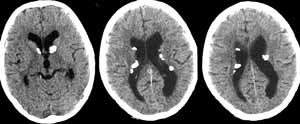

Больной У. 4 года. При поступлении жалобы на судорожные приступы, умственную отсталость, глубокую задержку психоречевого развития. Судороги кивательные, 1-2 серии в день. Ребенок ходит; СПР D<S, высокие. На теле выявлены депигментированные пятна размером до 12 мм. При проведении краниальной МРТ определяются очаги гиперинтенсивные в Т2W и изогипоинтенсивные в Т1W, расположенные преимущественно кортикально и субкортикально. Субэпендимальные очаги явно не визуализируются, возможно, вследствие кальцинации (Рис. 2). (Собственное наблюдение, исследование проведено на базе республиканской клинической психиатрической больницы; МР-томограф «Образ-2М» 0.14 Тл.).

[Увеличить]

Рис. 2. МР-томограммы головного мозга, Т2-взвешенные изображения. Выявляются множественные очаги гиперинтенсивные в Т2W.